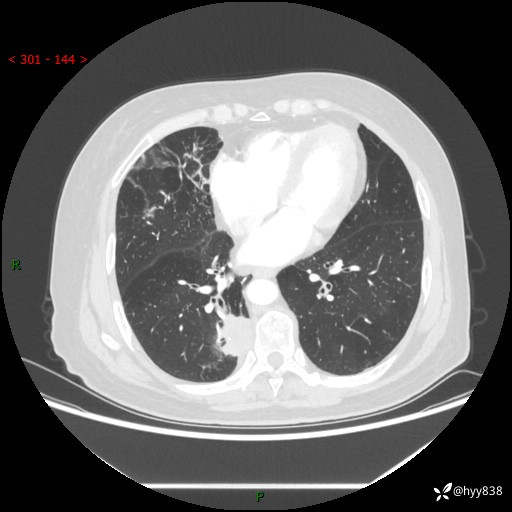

胸部CT肺窗(平扫外院)

辅助检查:CT

临床诊断:肺肿物